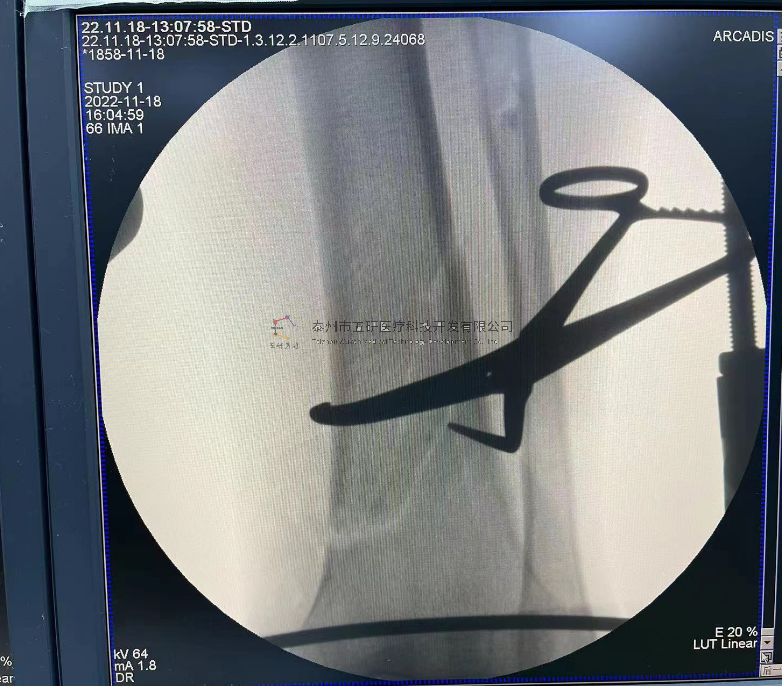

【基本資料】患者,男,41歲

本病例踝關(guān)節(jié)骨折。手術(shù)名稱(chēng):左踝關(guān)節(jié)骨折外固定支架手術(shù)

【手術(shù)資料】

8.png